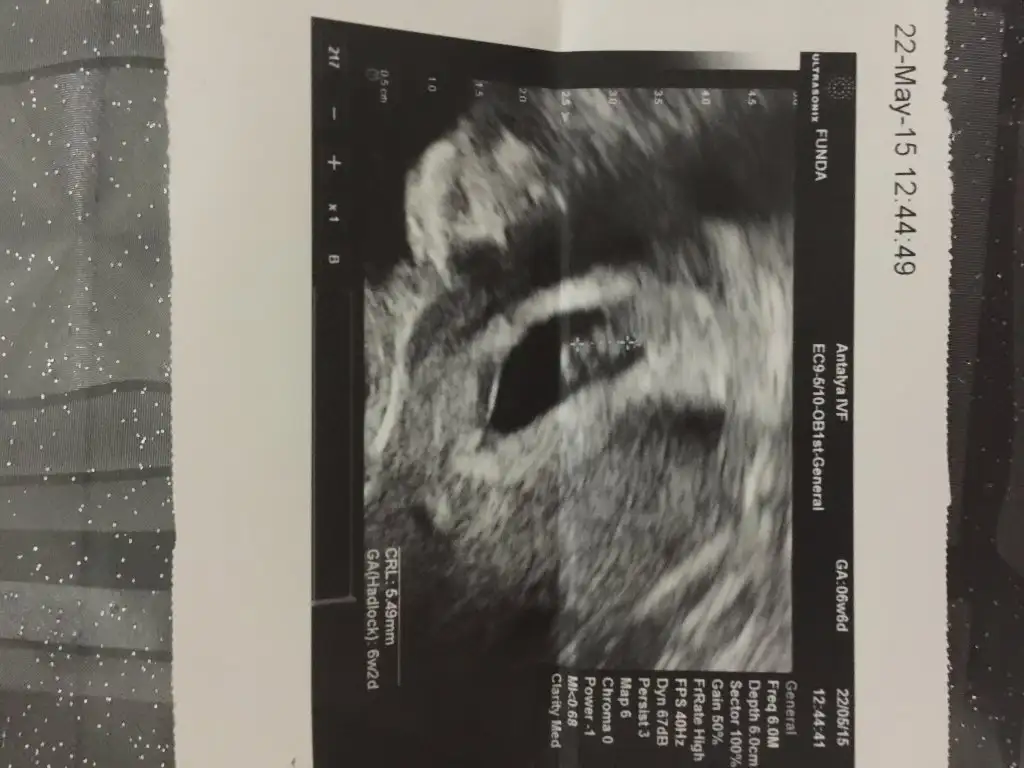

Kızlar resmi bugün aldım. 6.5 haftalık resimde sağda bir yüz göüyorum. Sizde görüyormusunuz yoksa ben Kafayı mı yiyom?

Eklentiler

• image.webp

image.webp

32,9 KB · Görüntüleme: 92